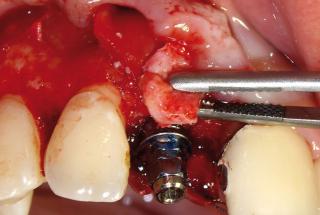

Clinical cases

MPI closely monitors clinical cases in the market to ensure their correct functioning and successful outcome.